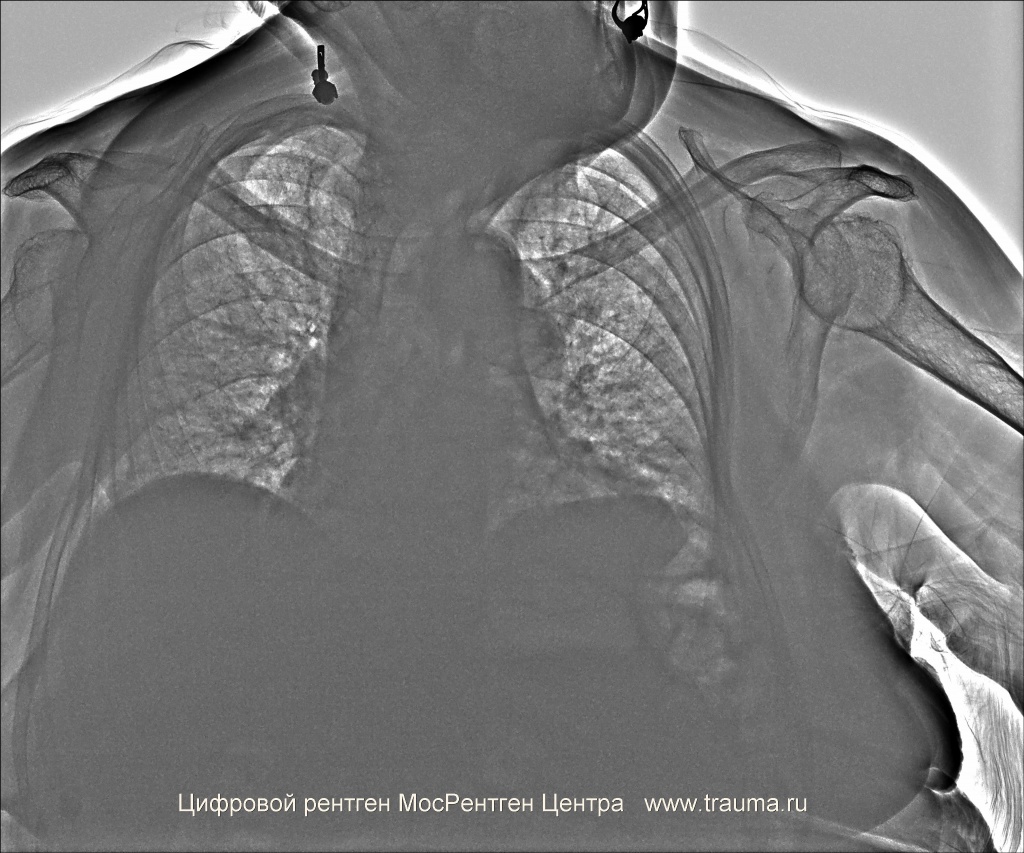

Эмфизема обозначена зелеными стрелками справа и слева.

Пульсоксиметр: 95%, ЧСС 116 в минуту, ЧДД 16 в минуту.

Проекции исследования: прямая задне-передняя проекция.

Положение пациента: сидит на табуретке.

ЭЭД: 0.2 мЗв.

Качество снимков: удовлетворительное.

Легочные поля: без очаговых и инфильтративных изменений.

Легочный рисунок: значительно ослаблен в верхних долях обоих легких, вплоть до его исчезновения. В нижней доле левого легкого множественные участки уплотнения размерами от 0,3 х 0,2 до 1 х 1,5 см (исход левосторонней нижнедолевой пневмонии)

Корни легких: уплотнены.

Синусы: свободны с обоих сторон.

Плевральная полость: газ не определяется.

Апикальная плевра: не изменена.

Междолевая плевра: не изменена.

Диафрагма: левый купол диафрагмы несколько уплощен, правый купол обычно расположен.

Сердце: без заметного увеличения отделов.

Аорта: кальциноз.

Тень средостения: не расширена, не смещена.

Контуры трахеи усилены, контуры бронхов не усилены.

Костная система: костная плотность снижена, костные разрастания на головке левой плечевой кости.

Заключение: Двусторонняя эмфизема. Пневмосклероз. Артроз левого плечевого сустава. Остеопороз. Хронический бронхит?